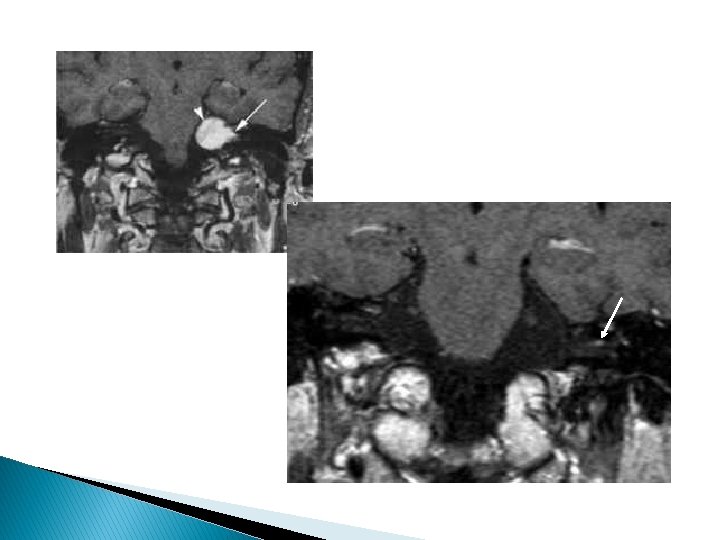

Hémangiome � Ganglion géniculé +++ � Hypersignal � Prise T 2 de contraste intense, progressive

� Lyse périlésionnelle � calcifications TDM